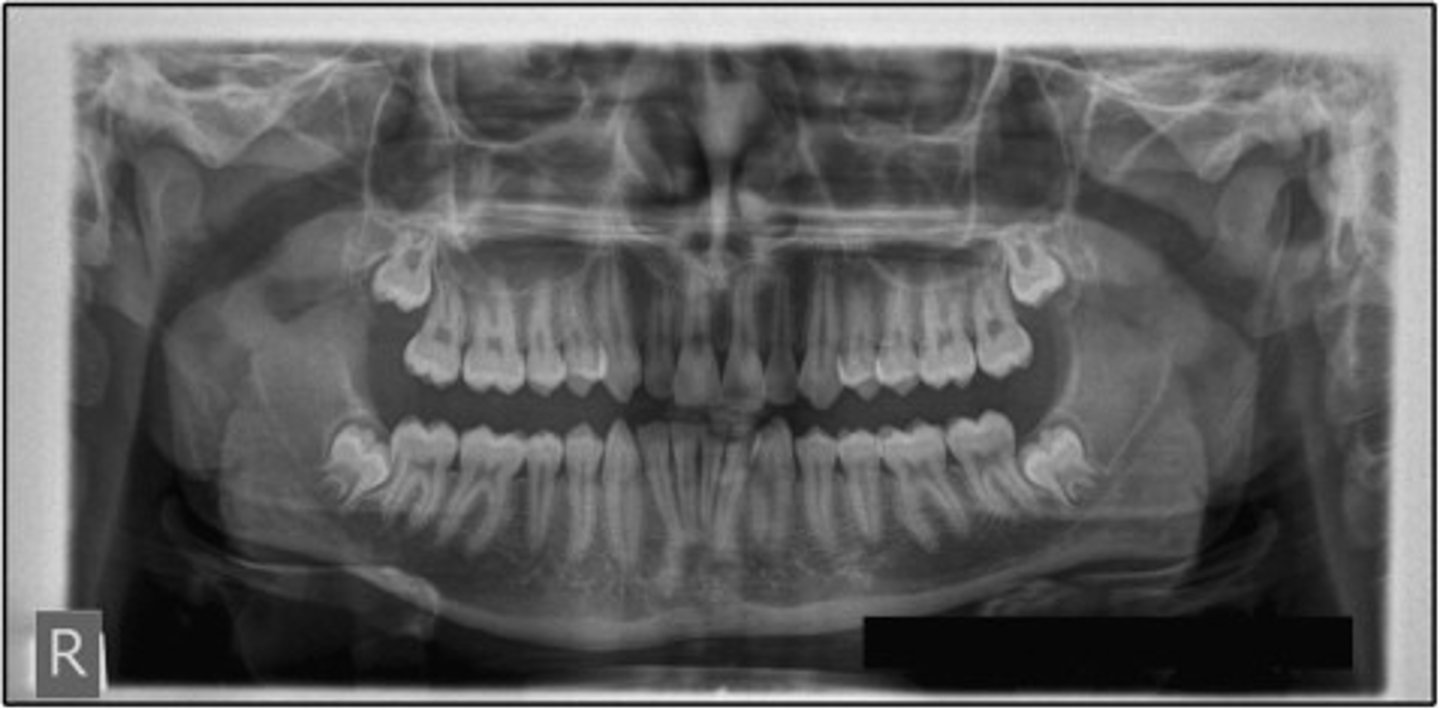

6 years old

How old is this child?

<p>How old is this child?</p>

14 years old